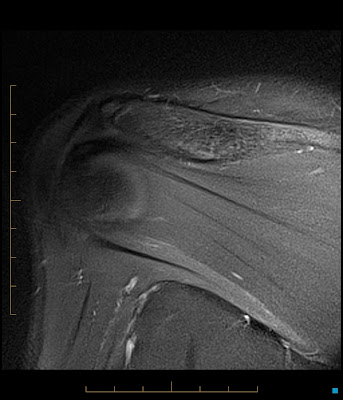

Reverse Hill Sachs

Labels:

Hill-Sachs,

MRI,

MSK,

Reverse Hill Sachs,

Shoulder